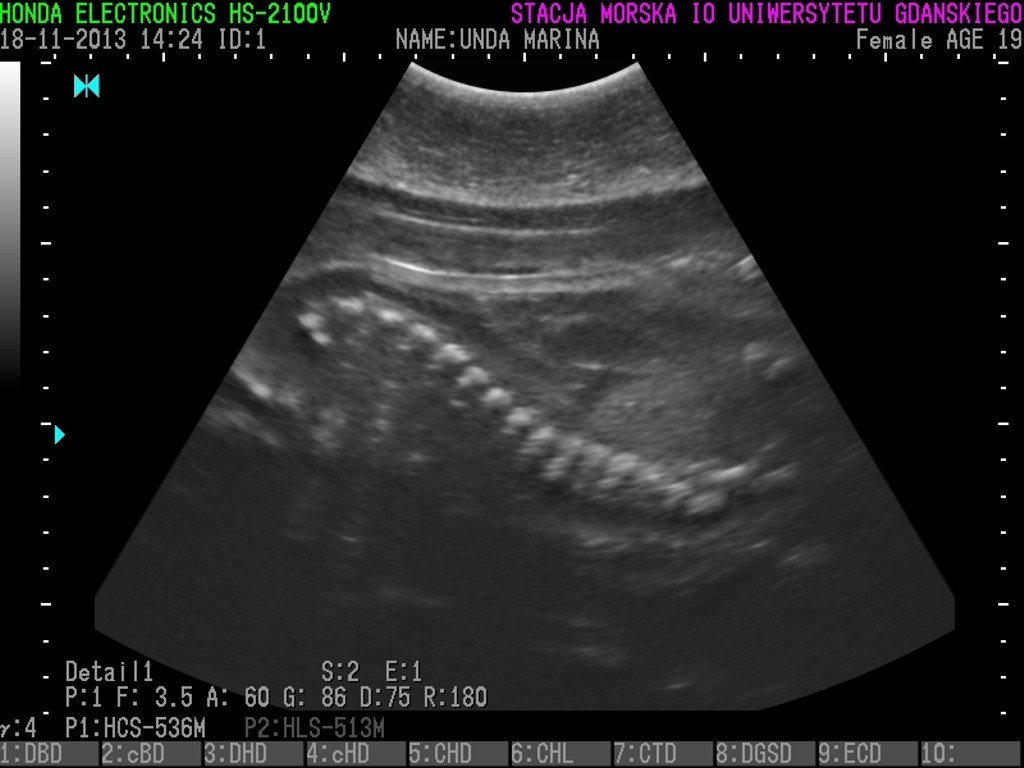

Unda Marina, foka znajdująca się w helskim fokarium, utraciła oczekiwanego potomka. Przyczyną była infekcja.

• Kilka dni temu opiekunowie zaniepokoili się faktem, że stała się apatyczna i straciła apetyt. Niezwłocznie pobrano krew i wykonano kontrolne badania. Bardzo wysoki poziom białych krwinek wskazywał na infekcję. Po konsultacjach z zagranicznym specjalistą podjęto decyzję o wprowadzeniu farmakologicznego leczenia. Niestety, bez dobrego skutku. Osłabiona, umieszczona w izolowanym basenie, poddawana jest antybiotykoterapii. Mamy nadzieję, że jej stan zdrowia poprawi się i Unda będzie mogła szybko dołączyć do reszty stada – czytamy Facebooku Fokarium.